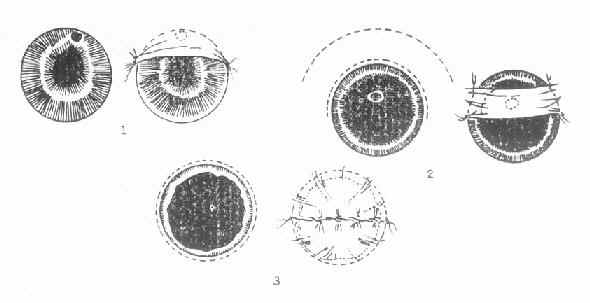

4.手术 (1)小结膜瓣遮盖术。当角膜溃疡有穿孔危险时,应将患眼轻轻加压包扎或戴角膜接触镜;口服降眼压药,以降低眼压,防止穿孔,必要时作结膜瓣遮盖术。如已穿孔,并有虹膜脱出时,可作虹膜切除兼结膜瓣遮盖术。遮盖术式视角膜溃疡的部位、面积大小而定。(图6-7)

图6-7 三种不同部位的角膜溃疡,采取不同的结膜瓣遮盖法

1.袋状;2.桥瓣状;3.荷包状